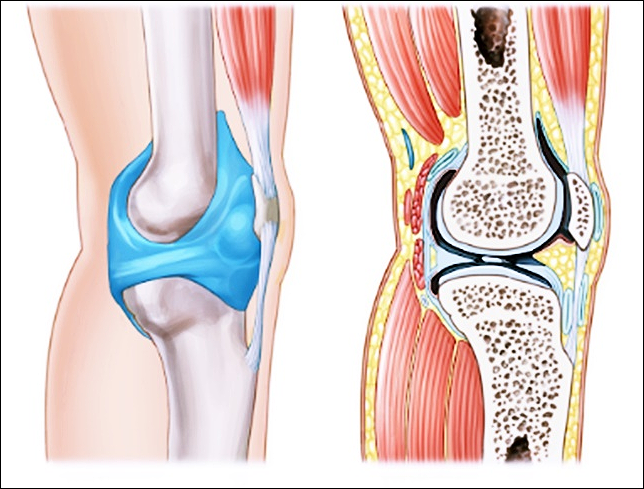

종근당 이모튼 캡슐의 효능은 크게 두가지가 있습니다. 퇴행성 관절염을 포함한 골관절염에 효과가 있습니다. 그리고 치주질환에도 도움이 됩니다. 치주질환으로 발생한 출혈과 통증을 제어하기 위한 보조적인 요법으로 활용될 수 있습니다. 그렇다면 종근당 이모튼 캡슐은 어떻게 복용해야 안전할까요? 다음을 참고하세요.